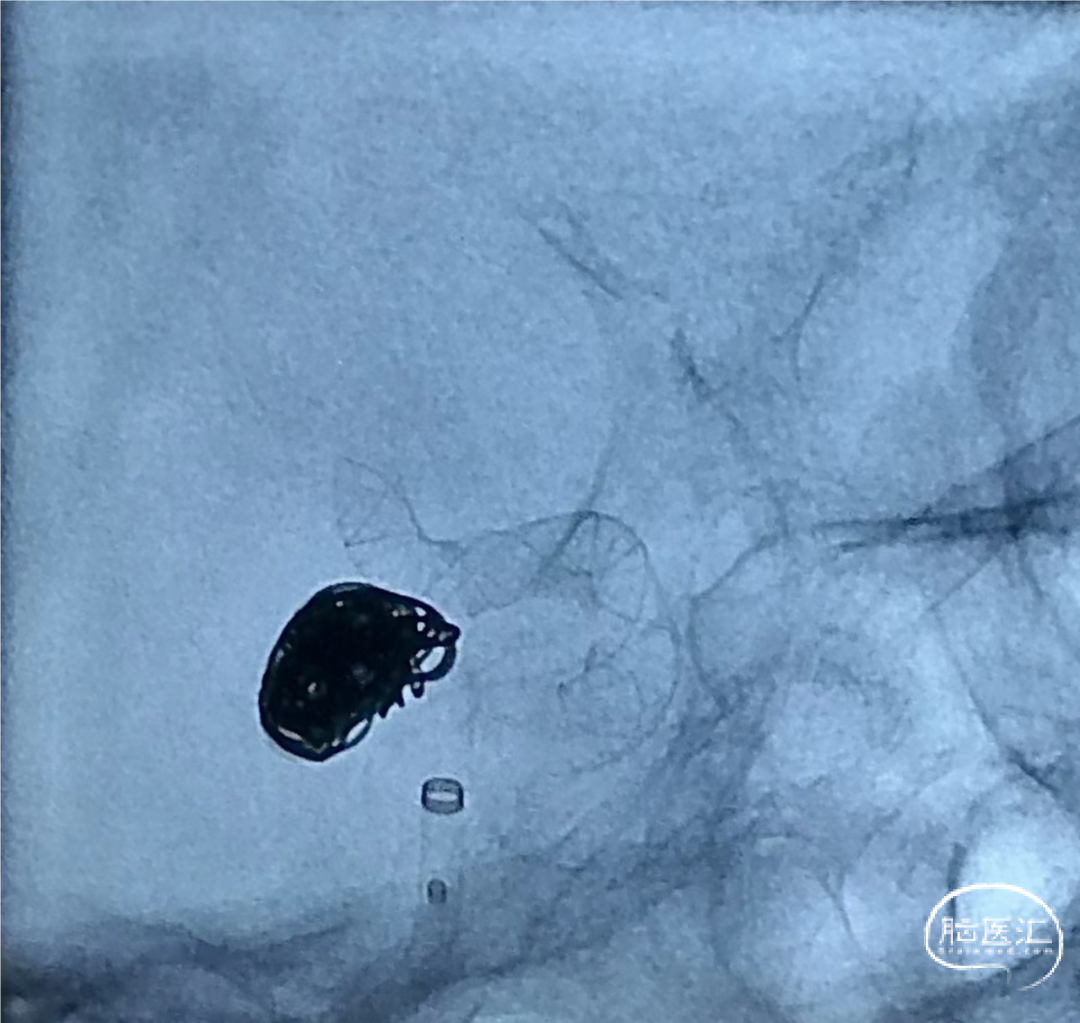

术前DSA造影:通过3D工作位测量动脉瘤大小约6.32mm*9.57mm,瘤颈宽约5.61mm,载瘤血管直径:近端直径3.85mm,远端直径3.62mm。

将泰杰TJMC18 Plus支架微导管越过瘤颈远端至少5cm,然后将预期血管内直径/长度为4.0mm*24mm的Nuva®密网支架输送到位,完成远端定位后,推拉结合缓慢半释放Nuva®密网支架。

术后即刻造影可见支架内血流通畅,动脉瘤内可见明显造影剂滞留,远端分支显影无缺失。